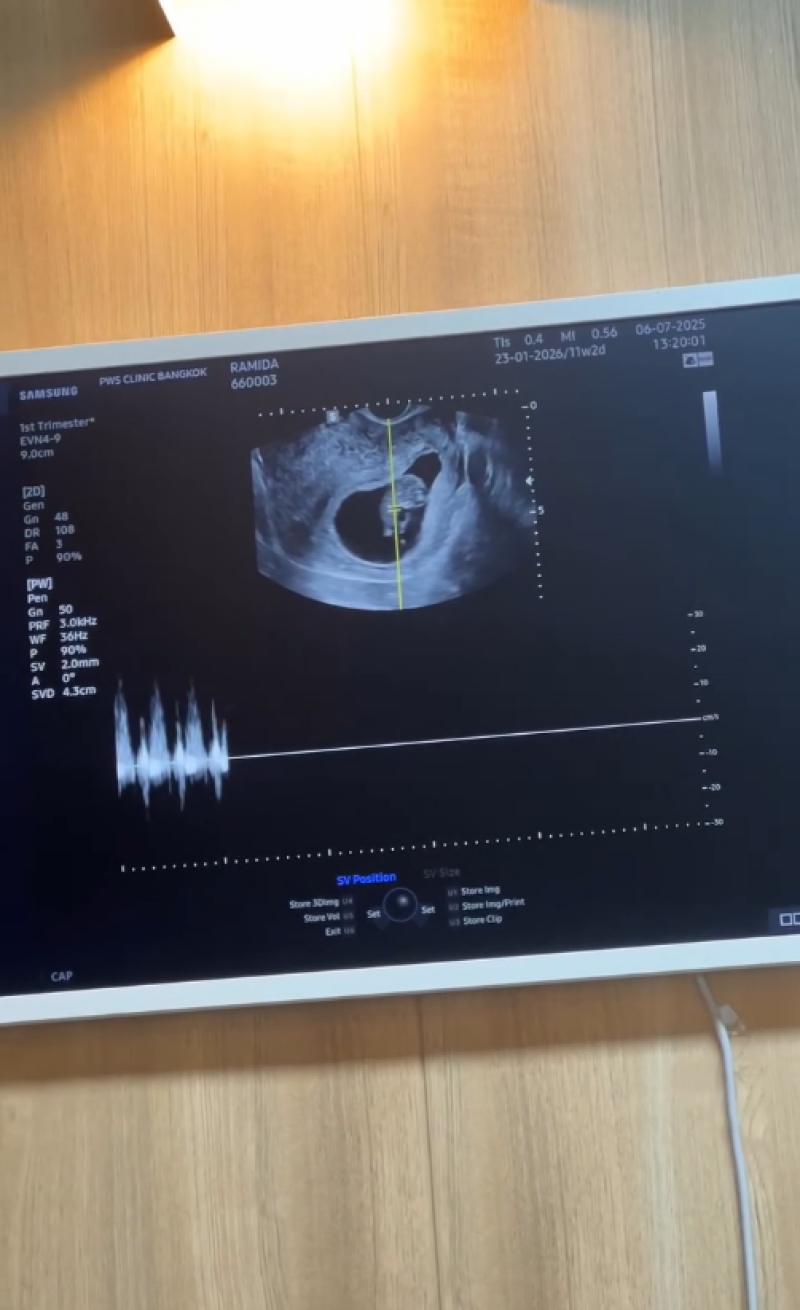

ขึ้นแท่นเป็นคุณพ่อคุณแม่ป้ายแดงเเล้วสำหรับ นุ่น รมิดา หลุยส์ สก๊อต ที่ก่อนหน้านี้ได้ออกมาประกาศข่าวดีตั้งท้องลูกคนแรก หลังใช้ชีวิตคู่ร่วมกันมาหลายปี ล่าสุดทั้งคู่ได้เผยคลิปวินาทีสำคัญขณะเข้ารับการตรวจอัลตร้าซาวด์ ผ่านอินสตาแกรมnoonrami

พร้อมแคปชั่นว่า วินาทีพ่อลูกได้เจอกัน 22june2568 #thefirsttimewemet #LRnewChapter129202 @louisscott ที่ต้องบอกเลยว่าทำเอา หลุยส์ หลั่งน้ำตาเลยทีเดียวหลังได้เห็นลูกครั้งแรก ท่ามกลางคนในวงการต่างแสดงความยินดีกันอย่างมาก